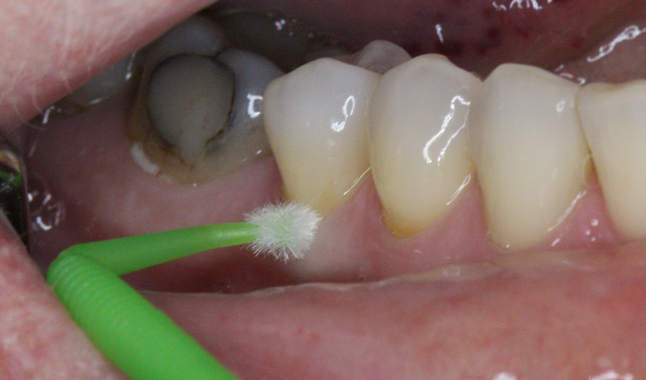

With our final area for treatment we moved to the symptomatic areas of sensitivity in the lower premolars. The surface was hard to the touch and did not require preparation. Universal adhesive [Futurabond U; VOCO] was massaged into the abfraction for 20 seconds as per the manufacturer’s instructions and cured.

Desensitization achieved through single layer application of universal adhesive [Futurabond U; VOCO].

Desensitization achieved through single layer application of universal adhesive [Futurabond U; VOCO]

Cooler than room temperature water was given to the patient to swish, and she was able to verify that significant improvement had been achieved.